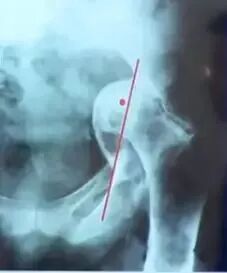

Pradhan法测量:髋臼假体前倾角在X线片上标记髋臼杯口形成椭圆的最大直径D,在最大直径的1/5处标记点M,经过点M做最大直径的垂线并与椭圆相交于两点A、B。测量最大直径D和点M到点A或B的距离P,则髋臼前倾角为

髋臼假体位置评估:

Hubard法:

①在X线上两侧闭孔上缘连线与通过髋臼外上角垂线的交点为A;

②点A线上1/4骨盆高度处为B,再在闭孔连线上作点C,使AC=AB;

③以A为中心,以AB为半径做圆弧BC,正常髋臼应在此等腰三角扇形内。

股骨假体评估:

①柄-髓腔轴线夹角;

②通过正位X线片上测量假体柄长轴与股骨长轴间夹角来确定,夹角≤3°为中心固定;

③超出3°为内翻或外翻固定;

——远端尖端在外侧-内翻

——远端尖端在内侧-外翻

前倾角:10°-15°;

必须由侧位片评估。

注意:部分假体自带前倾角(绝大多数不带),术中应予注意,以免术中再前倾放置引起前倾过度。